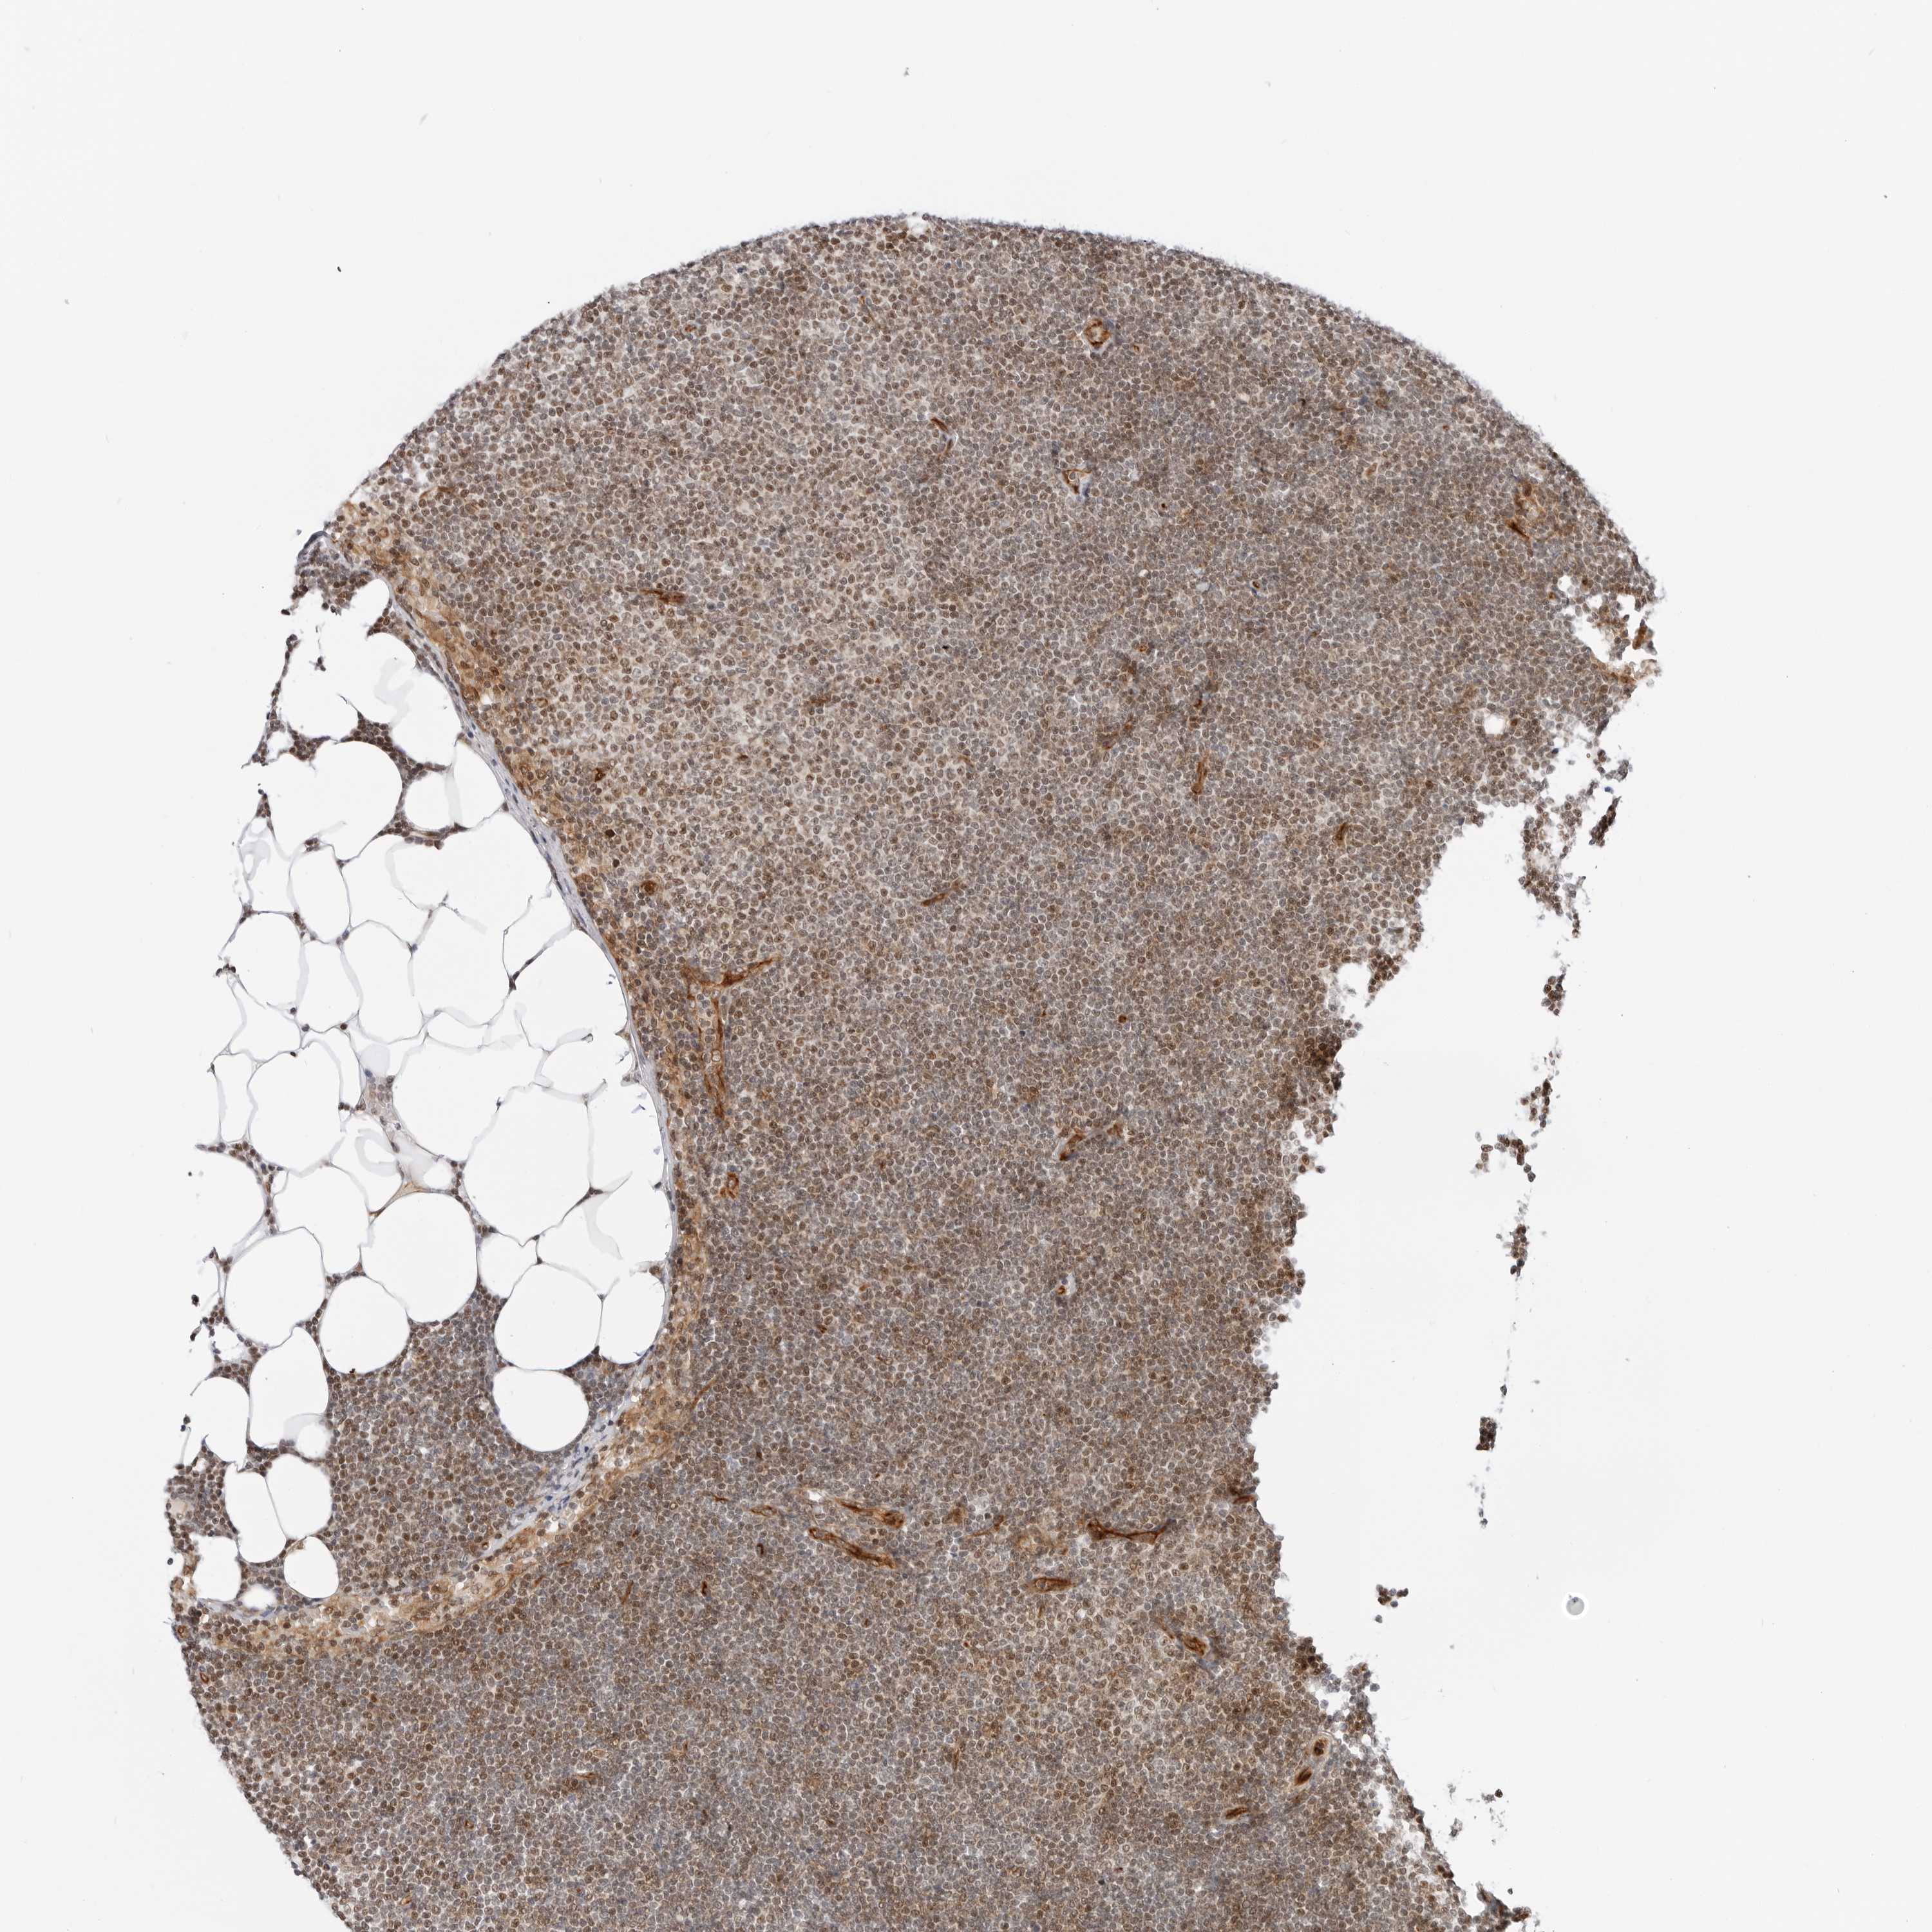

CANCER LYMPHOMA Show tissue menu

LYMPHOMA - Protein expressioni

A mouse-over function shows sample information and annotation data. Click on an image to view it in a full screen mode. Samples can be filtered based on level of antibody staining by selecting one or several of the following categories: high, medium, low and not detected. The assay and annotation is described here.

Each image is clickable and will lead to virtual microscopy that enables deeper exploration of all samples and also displays staining intensity scores, fraction scores and subcellular localization as well as patient and tissue information for each sample.

Antibody HPA026833

Staining

High

Strong

>75%

Location

Nuclear

Hodgkin's disease, NOS

Malignant lymphoma, non-Hodgkin's type, High grade

Malignant lymphoma, non-Hodgkin's type, Low grade